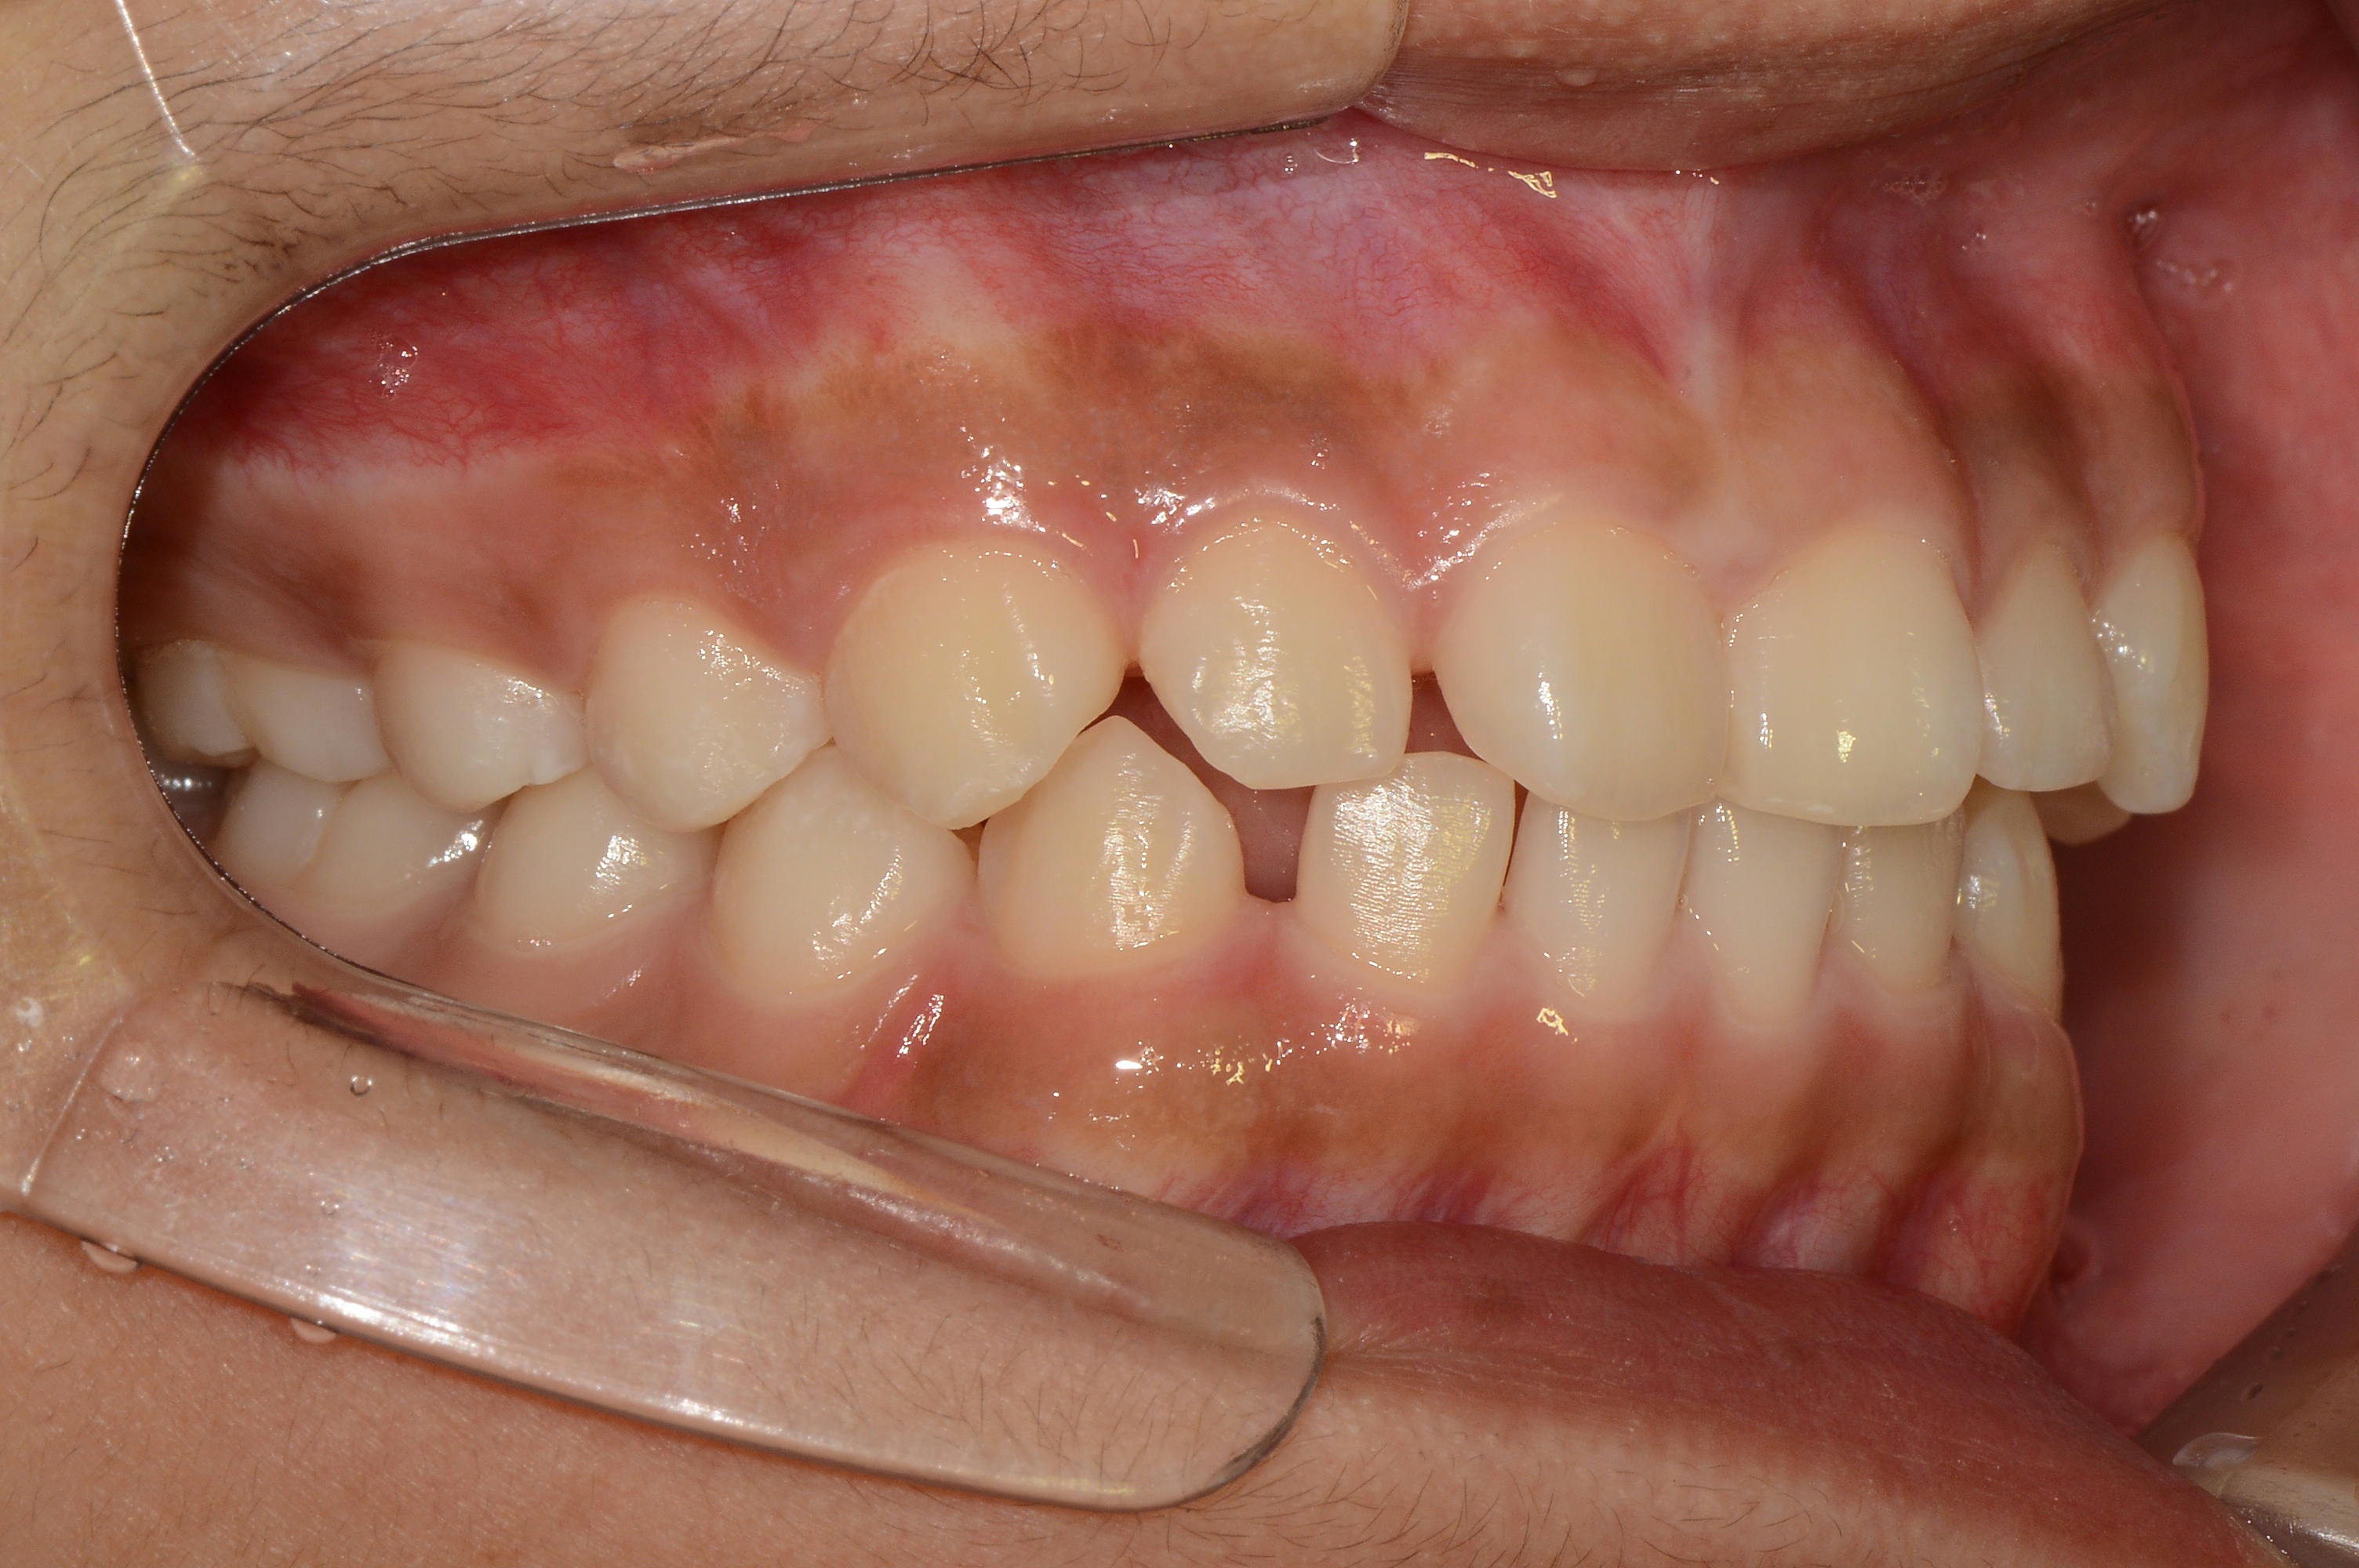

치료 전 사진입니다.